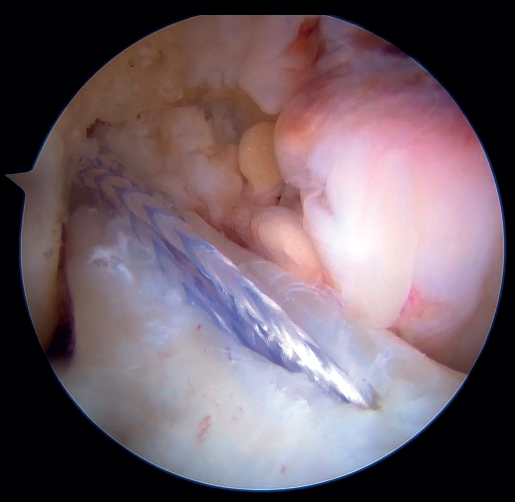

Our attention now turns to outside the knee, where the loop of the cortical suspension system (ACL Repair TightRope®) is secured to the ACL using the FiberRing® sutures. This device is a cortical suspension button with a loop of variable length, which also incorporates a high strength tape. To secure it, the suture marked as "1" on the card is first passed through the retriever thread of one of the FiberRing® sutures, and then the step is repeated through the retriever thread of the remaining FiberRing® suture. Next, this thread passing through the rings of the FiberRing® system is passed through the closed loop marked as "2". Finally, this thread is passed through the nitinol marked "3"; the card is held firmly and the nitinol is pulled so that the TightRope® thread passes through the cortical plate. At this point, part of the loop, the button and the threads connected to it (loop traction sutures, button lift sutures and high strength tape) remain outside the knee, waiting to be inserted into the joint (Figure 8).

The next step is to remove the femoral retriever thread through the cannula of the anteromedial portal, loading it with the traction and flipping sutures, but not with the high strength tape. By pulling on the retriever thread, the ACL RepairTightRope® sutures will pass through the femoral tunnel (Figure 9), exiting through the skin. Using the lift sutures, the button is then likewise advanced through the tunnel until it is flipped over the lateral femoral cortex (which can be checked by pulling firmly on the high strength tape, which still exits through the cannula). At this point, all that remains is to pull alternately on both loop traction sutures to shorten the loop and reduce the stump of the ACL until contact is made with its native footprint.

As the last step of the procedure, the high strength tape connected to the cortical button is retrieved through the anteromedial portal, where the tibial tunnel retriever thread is located. By loading the tape onto the thread and pulling on it, the tape now lies in front of the repaired ligament and exits through the anteromedial cortex of the tibia, where it is fixed with the knee fully extended with a tenodesis implant (SwiveLock®, HealiCoil®). After completing the procedure, it is advisable to check the tension of the ligament and the InternalBrace®, as well as the absence of impingements and limitations in mobility of the knee (Figure 10).